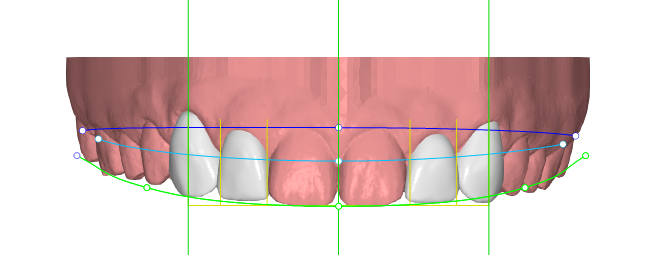

Paciente joven que acababa de finalizar su tratamiento de ortodoncia. Aunque estaba satisfecho con el resultado general, no se sentía cómodo con las troneras incisales que habían quedado entre los laterales y los caninos. Buscaba una solución rápida, estética y mínimamente invasiva

Desde Elevantia Solutions propusimos un Injectable Composite Design con carillas únicamente en esas piezas, para cerrar los espacios sin necesidad de limar sus dientes. Se trabajaron varias versiones del diseño hasta conseguir un resultado totalmente adaptado a sus expectativas, respetando al máximo la estructura dental natural al cerrar los espacios